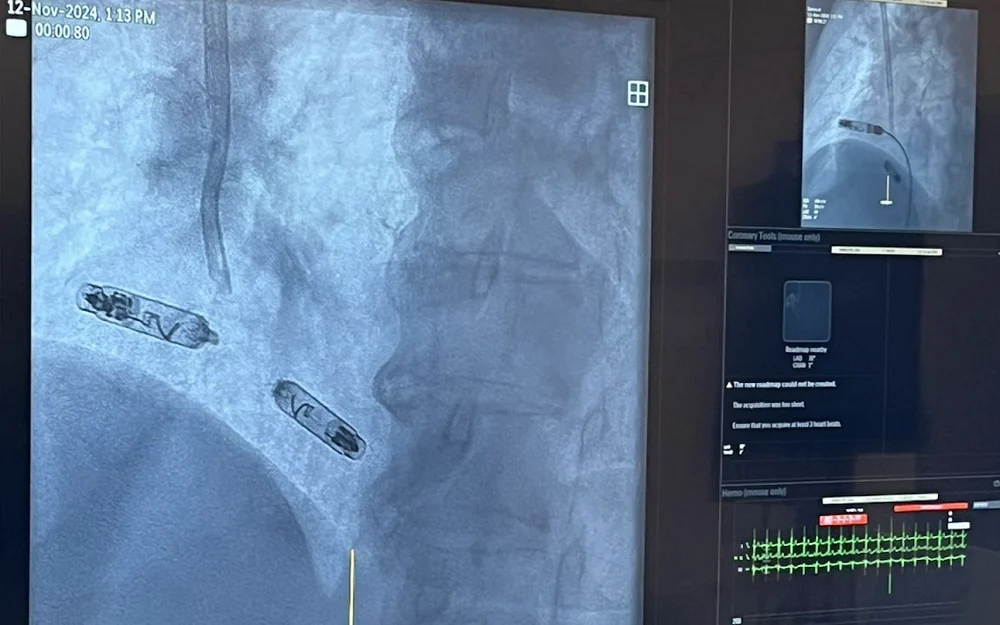

We wtorek 12 listopada 2024 roku odbyły się pierwsze na Śląsku zabiegi wszczepienia nowego bez elektrodowego dwujamowego stymulatora serca. Zabiegi z zastosowaniem nowej technologii odbyły się w III Katedrze i Klinice Kardiologii Śląskiego Centrum Chorób Serca w Zabrzu.

Zaimplantowany pacjentkom podczas wtorkowych zabiegów w Śląskim Centrum Chorób Serca innowacyjny system do elektroterapii kardiologicznej to pierwszy dwukomorowy bezelektrodowy stymulator serca.

– Nowy system do stymulacji bezelektrodowej to dwa stymulatory -„kapsułki” o wielkości mniejszej niż bateria AAA (to około jednej dziesiątej wielkości tradycyjnego stymulatora serca). Po zaimplantowaniu i aktywacji stymulatory-kapsułki komunikują się ze sobą niskonapięciowymi impulsami, dzięki czemu możliwa jest nie tylko stała stymulacja serca, ale także jednoczesna właściwa synchronizacja między pracą prawego przedsionka i prawej komory serca pacjenta. W nowym systemie możliwa jest także stymulacja DDD, „na żądanie” stymulacji przedsionków i na żądanie stymulacji komór. Te możliwości przekładają się na jeszcze skuteczniejszą terapię bradykardii i jeszcze lepszą jakość życia pacjenta po wdrożeniu terapii – tłumaczy dr hab. n. med. Mateusz Tajstra.